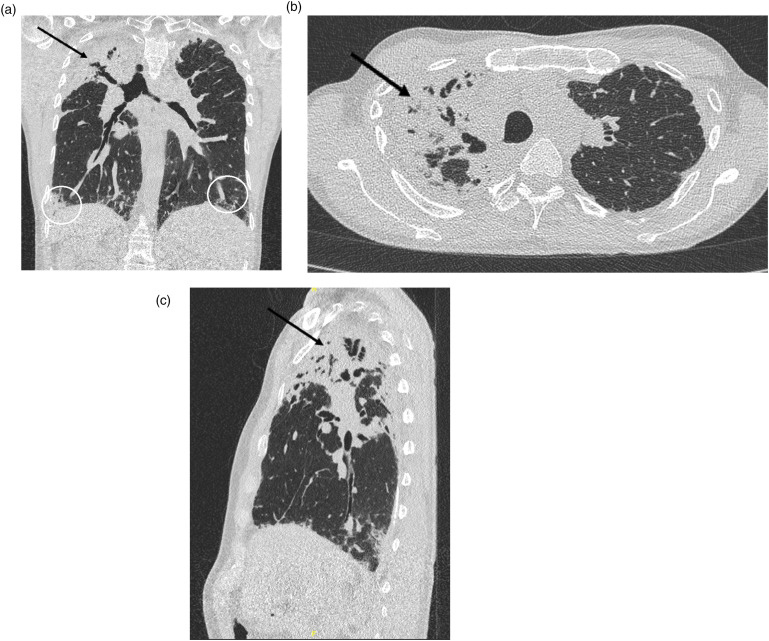

Case presentationDescription of a patient with a progressive destructive lung disease resembling pleuroparenchymal fibroelastosis, liver cirrhosis and bone marrow changes. Genetic workup identified a rare heterozygous coding variant in the TERT (telomerase reverse transcriptase) gene c.472 C>T; p.(Leu158Phe) and telomere length testing revealed significant telomere shortening, supporting the diagnosis of telomere biology disorder (TBD).DiscussionTBD is an underrecognized cause of interstitial lung disease (ILD). It is a heterogeneous disease that can affect different organs, including lungs, liver and bone marrow. Genetic testing in ILD is crucial for early diagnosis, risk assessment, and family screening. Identifying this variant enables targeted genetic testing for relatives, allowing preventive measures and lifestyle modifications.